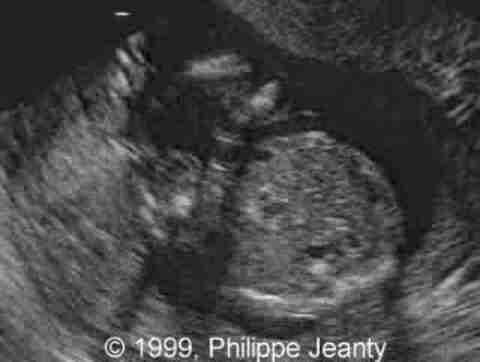

17-year-old primigravida.

This examination is obtained at 18 weeks amenorrhea.

What is your suspected diagnosis ? How would you confirm it ?

Many of you came up with numerous abnormal findings and indeed this baby had many including:

• abnormal fingers,

• micrognathia,

• abnormal cardiac axis

• small stomach

• large eyes and possibly buphophtalmos

• many other small findings…

Very few, however, made the most crucial observation: the great disproportion between the head and abdomen. That disproportion is very typical of triploidy (see the lecture on aneuploidy for another example) and I know of no other conditions where such a big difference exist without a concomitant intracranial anomaly such as hydrocephaly, or teratomas… Of course, one of you will come up with a great differential diagnosis and then we will learn even more !

Teaching point: A head much greater than the abdomen is a strong sign of triploidy.